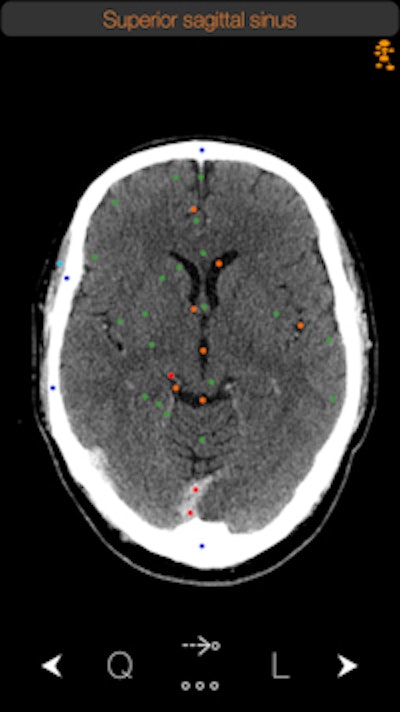

The CT Anatomy app. Image courtesy of iCat Medical.Originally a radiographer at a hospital in the U.K., Michalopoulos was frustrated by the lack of real-world apps that displayed human anatomy. Apps based on medical illustrations were available, "but you never see illustrations in real life in CT," he told AuntMinnie.com.

CT Anatomy educates users on the appearance of normal human anatomy as seen on CT. The images are based on actual human scans that are scrubbed of identifying information.

iCat has recorded more than 15,000 downloads of CT Anatomy from the iTunes App Store. The software is available as a standalone offering for $9.99 or as part of a bundle with two other apps: X-Ray Anatomy and a radiography positioning atlas.

CT Anatomy is currently on version 6, but iCat hopes to make version 7 available this month. The new iteration includes better navigation with one-finger scrolling, easier navigation between the mediastinum and lung windows, and various bug fixes. What's more, iCat has doubled the number of chest images available, shifting from 25 to 50.